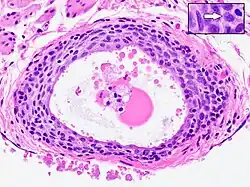

Walthard cell rest

- Cyst (may also be solid nest) of transitional type epithelium.

- Eosinophilic luminal secretions.

- Uniform nuclei with irregular borders and nuclear grooves (insert image).

Walthard cell rests, sometimes called Walthard cell nests, are a benign cluster of epithelial cells most commonly found in the connective tissue of the fallopian tubes, but also seen in the mesovarium, mesosalpinx and ovarian hilus.

Appearance

They appear as white/yellow cysts or nodules that can reach a size of 2 millimeters. They typically have elliptical nuclei with a long groove (along the major axis) – so-called "coffee bean" nuclei.